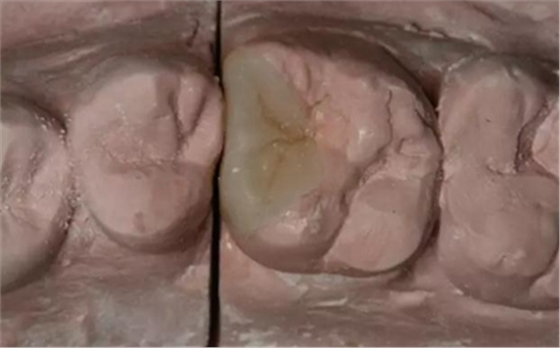

改良垂直褥式縫合關(guān)閉傷口,傷口無明顯滲血,高嵌體預(yù)備完畢后,硅橡膠取模,見邊緣清晰。灌注模型,模型上3MZ350XT分層堆塑高嵌體。

一周后拆除縫線,試戴高嵌體,試戴合適后雙固化粘結(jié)。調(diào)合,拋光。